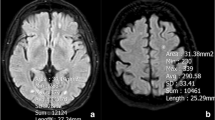

Initially, white matter hyperintensities in axial T2/FLAIR sequences of cerebral MRI were graded based on the Fazekas score [11]. In the manuscript, the term “T2-/FLAIR white matter hyperintensities” is replaced by the shorter synonymous term “white matter lesions” (WML). Degree of WML was defined as follows: no WML (grade 0), punctate WML (grade 1), beginning confluence of WML (grade 2) and large confluent areas (grade 3). Representative examples of WML grades are shown in Fig. 1.

Secondly, the NoM was determined on axial 3D T1-weighted sequences of cerebral MRI, and the maximum axial diameter of each individual metastasis was measured. Metastases situated in deep white matter were termed white matter metastasis (WMM) as these might have a different vascular background than metastases at the border of grey and white matter [12]. The per-patient mean diameter of all metastases (mDM) was determined.